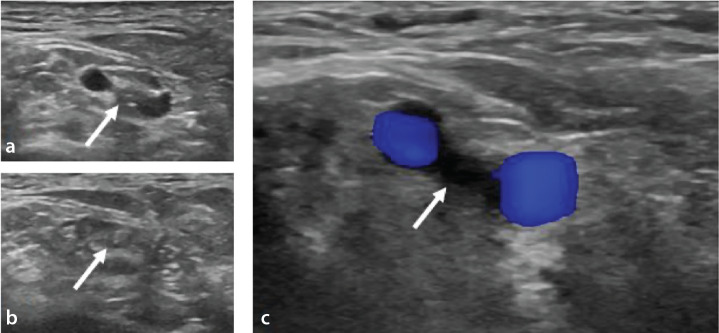

Purpose: Peripheral arterial disease (PAD) is increasingly prevalent, particularly among the aging population. Retrograde tibiopedal access (RTPA) has emerged as a useful endovascular treatment for PAD. However, there is limited research examining factors that influence the efficacy of RTPA. To investigate factors affecting the access, crossing, and recanalization success rates of RTPA for infrapopliteal PAD treatment.

Methods: A retrospective study was conducted on 720 patients who underwent endovascular treatment for PAD. Of these, 104 patients (mean age: 65.5 ± 16.2; 89 men) with 131 RTPA trials were included in the final evaluation. The disease and its duration, Rutherford score, smoking status, access site, and its occlusion status, access, crossing, and recanalization success were noted. Data were analyzed using Pearson's chi-square and Mann-Whitney U tests and multivariate logistic regression to evaluate the impact of various factors on success rates.

Results: The access success rate was 82.6%, the crossing success rate was 95.4%, and the recanalization success rate was 74%. Access success was significantly higher when the dorsal pedal artery (DPA) was the access artery compared with the posterior tibial artery (91.3% vs. 74.2%, P = 0.009). Access success was notably lower in patients with thromboangiitis obliterans compared with patients with diabetes mellitus (DM) and non-DM atherosclerosis (68.6% vs. 90.3% and 80.3%, P = 0.019). Recanalization success was higher when the puncture site was non-occluded (76.7% vs. 53.5%, P = 0.023).

Conclusion: The study suggests that RTPA is a generally effective and safe technique for infrapopliteal PAD treatment. The most favorable outcomes are observed in individuals with DM who have a non-occluded DPA at the puncture site. Recanalization success is only affected by the patency of the artery at the puncture site.